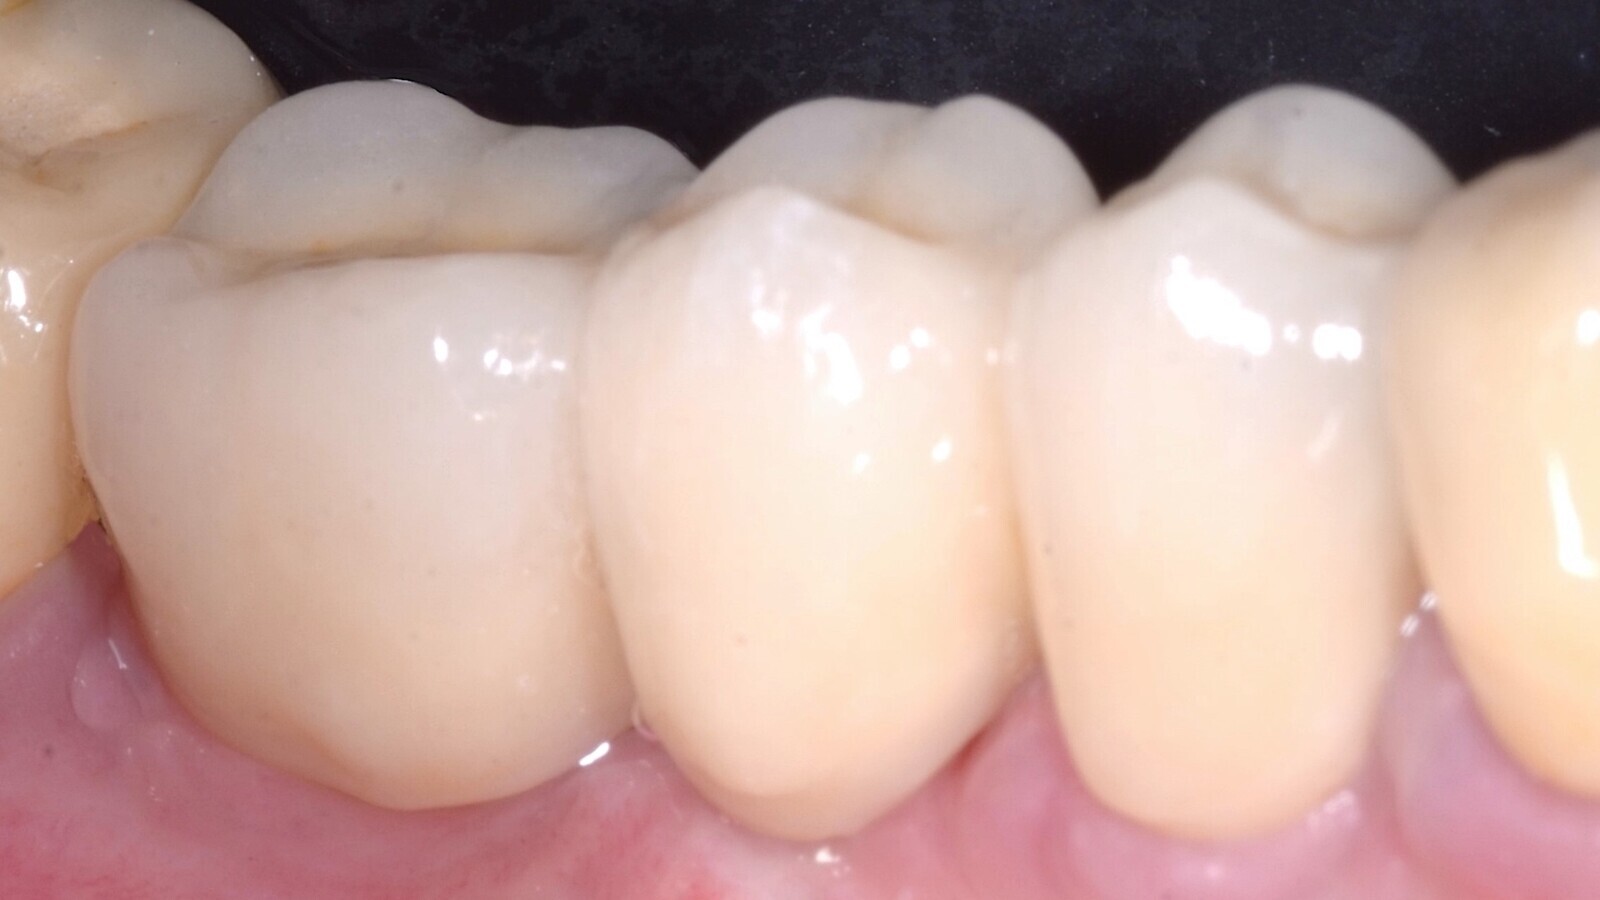

Aproximadamente un año después de la entrega de las prótesis, la paciente mostraba un excelente aspecto de los tejidos blandos, así como un perfil estético correctamente restaurado (Fig. 12).

Fig. 12. El seguimiento a 1 año después de la colocación de la prótesis definitiva muestra el excelente aspecto de los tejidos blandos.